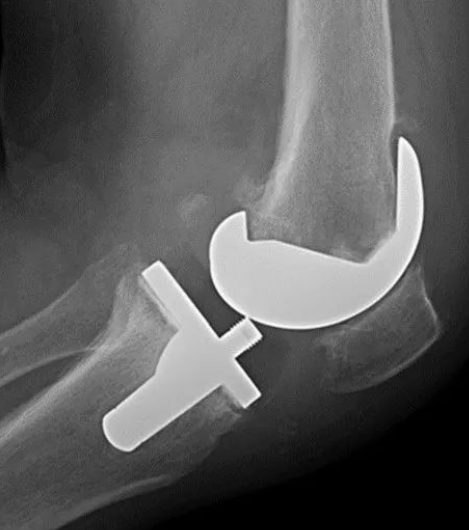

膝关节置换术后早期与晚期失败案例!